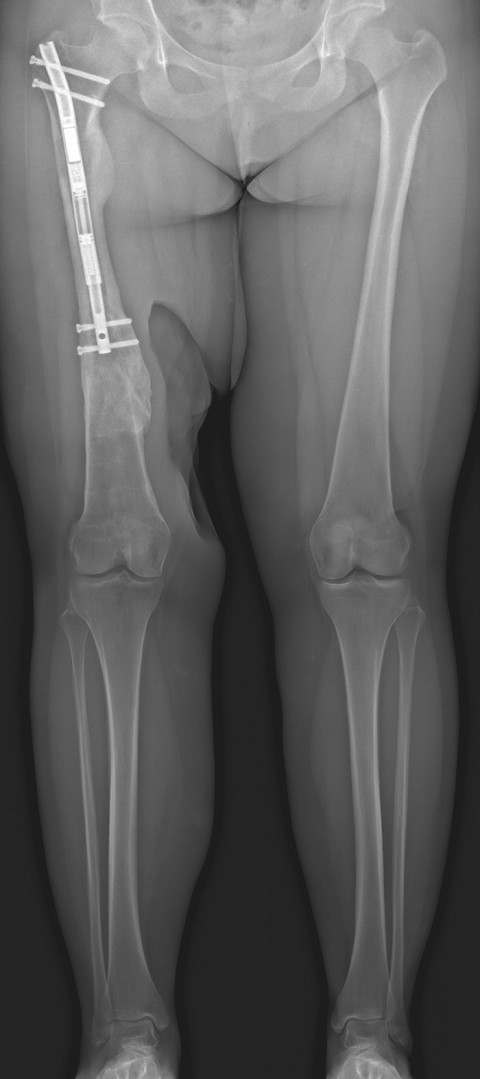

Gemeinsam mit der Patientin entschieden wir, zunächst den Nagel zu entfernen und den Oberschenkel im Bereich der Pseudarthrose zu stabilisieren, um gleichzeitig mit der Verheilung des Knochens auch die Achse korrigieren zu können. Dies gelang erfreulicherweise unkompliziert, es blieb jedoch die ausgeprägte Beinlängendifferenz aufgrund des um 3.5 cm verkürzten Oberschenkels (Bild 2).

Aufgrund der nun noch persistierenden Beinlängendifferenz entschlossen wir uns zu einer Verlängerung des Oberschenkelknochens mit dem magnetgetriebenen Precice®-Marknagel. So konnten wir den Oberschenkel schlussendlich mit diesem Nagel problemlos um 3.5 cm verlängern (Bild 3).